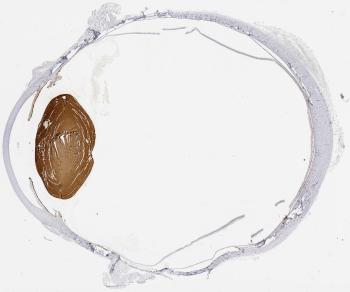

The beta-crystallin B2 protein, encoded by the CRYBB2 gene, is a very important structural component of the human eye lens. Immunohistochemical staining of CRYBB2 protein shows specific expression in the lens.

We highlight one of the beta crystallin proteins CRYBB2 expressed in the lens. Within the Human Protein Atlas 53 genes are shown to be expressed in the human eye. Visit the Eye proteome page for more information about the human eye and its proteins.